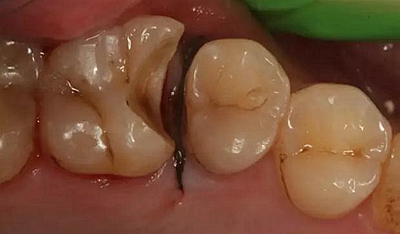

病例一 女性,20歲,大學生,要求補牙,檢查口內(nèi)可見A6大面積缺損,近中牙齦息肉,拍X片,根管充填物略差,但根周未見明顯陰影,口內(nèi)檢查無叩痛。建議患者冠延長手術+高嵌體修復。

患牙遠中邊緣嵴完整,強度沒有降低,故擬保留遠中邊緣嵴,高嵌體修復。首先去除腐質(zhì)及原墊底材料,流體樹脂+3M Z350XT樹脂墊底。局麻下行冠延長手術。在此需要提及個人的一個觀點。冠延長手術原則上要求3-6個月以上才能永久修復。但是個人喜歡后牙肩臺建立在齦上,所以修復后的修復體邊緣位于牙齦上方1mm,對牙周的愈合影響較?。ㄈ绻麨辇l下邊緣則要慎重),故該患者術中按照齦上邊緣的設計進行冠延長手術。以下為術中:

改良垂直褥式縫合關閉傷口,傷口無明顯滲血,高嵌體預備完畢后,硅橡膠取模,見邊緣清晰。灌注模型,模型上3MZ350XT分層堆塑高嵌體。

一周后拆除縫線,試戴高嵌體,試戴合適后雙固化粘結。調(diào)合,拋光。